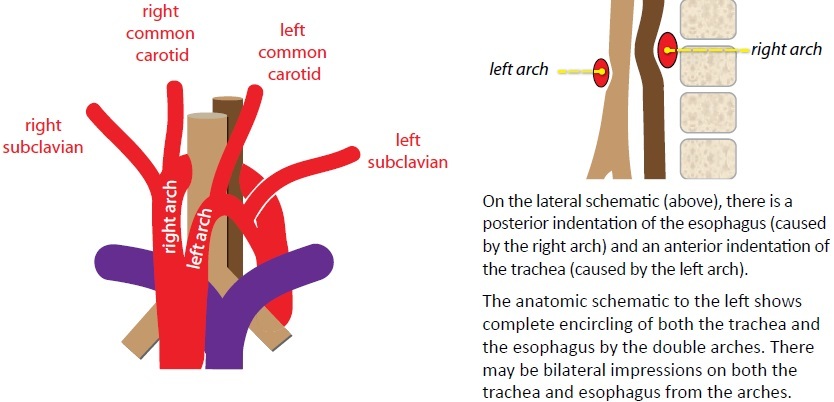

Complete encircling of the trachea and esophagus by the aortic arch or great vessels is a vascular ring.

The double aortic arch and right arch with aberrant left subclavian artery look the same on radiography/esophagram, each producing a posterior impression on the esophagus.

Double aortic arch

Double aortic arch is the most common vascular ring. The arches encircle both the trachea and esophagus, adn may cause stridor.

The right arch is usually superior and larger in caliber than the left.

For presurgical planning, the goal of the radiologist is to determine which arch is dominant, typically with MR; the surgeon will then ligate the non-dominant arch to alleviate the stridor.

Right arch with aberrant left subclavian artery

The second most common vascular ring is a right aortic arch with an aberrant left subclavian artery. The right arch indents the anterior trachea while the aberrant left subclavian artery wraps posteriorly around the esophagus. The ring is completed by the ligamentum arteriosum.

On the frontal view, a right arch with aberrant left subclavian artery produces a leftward impression/deviation of the tracea by the right aortic arch.